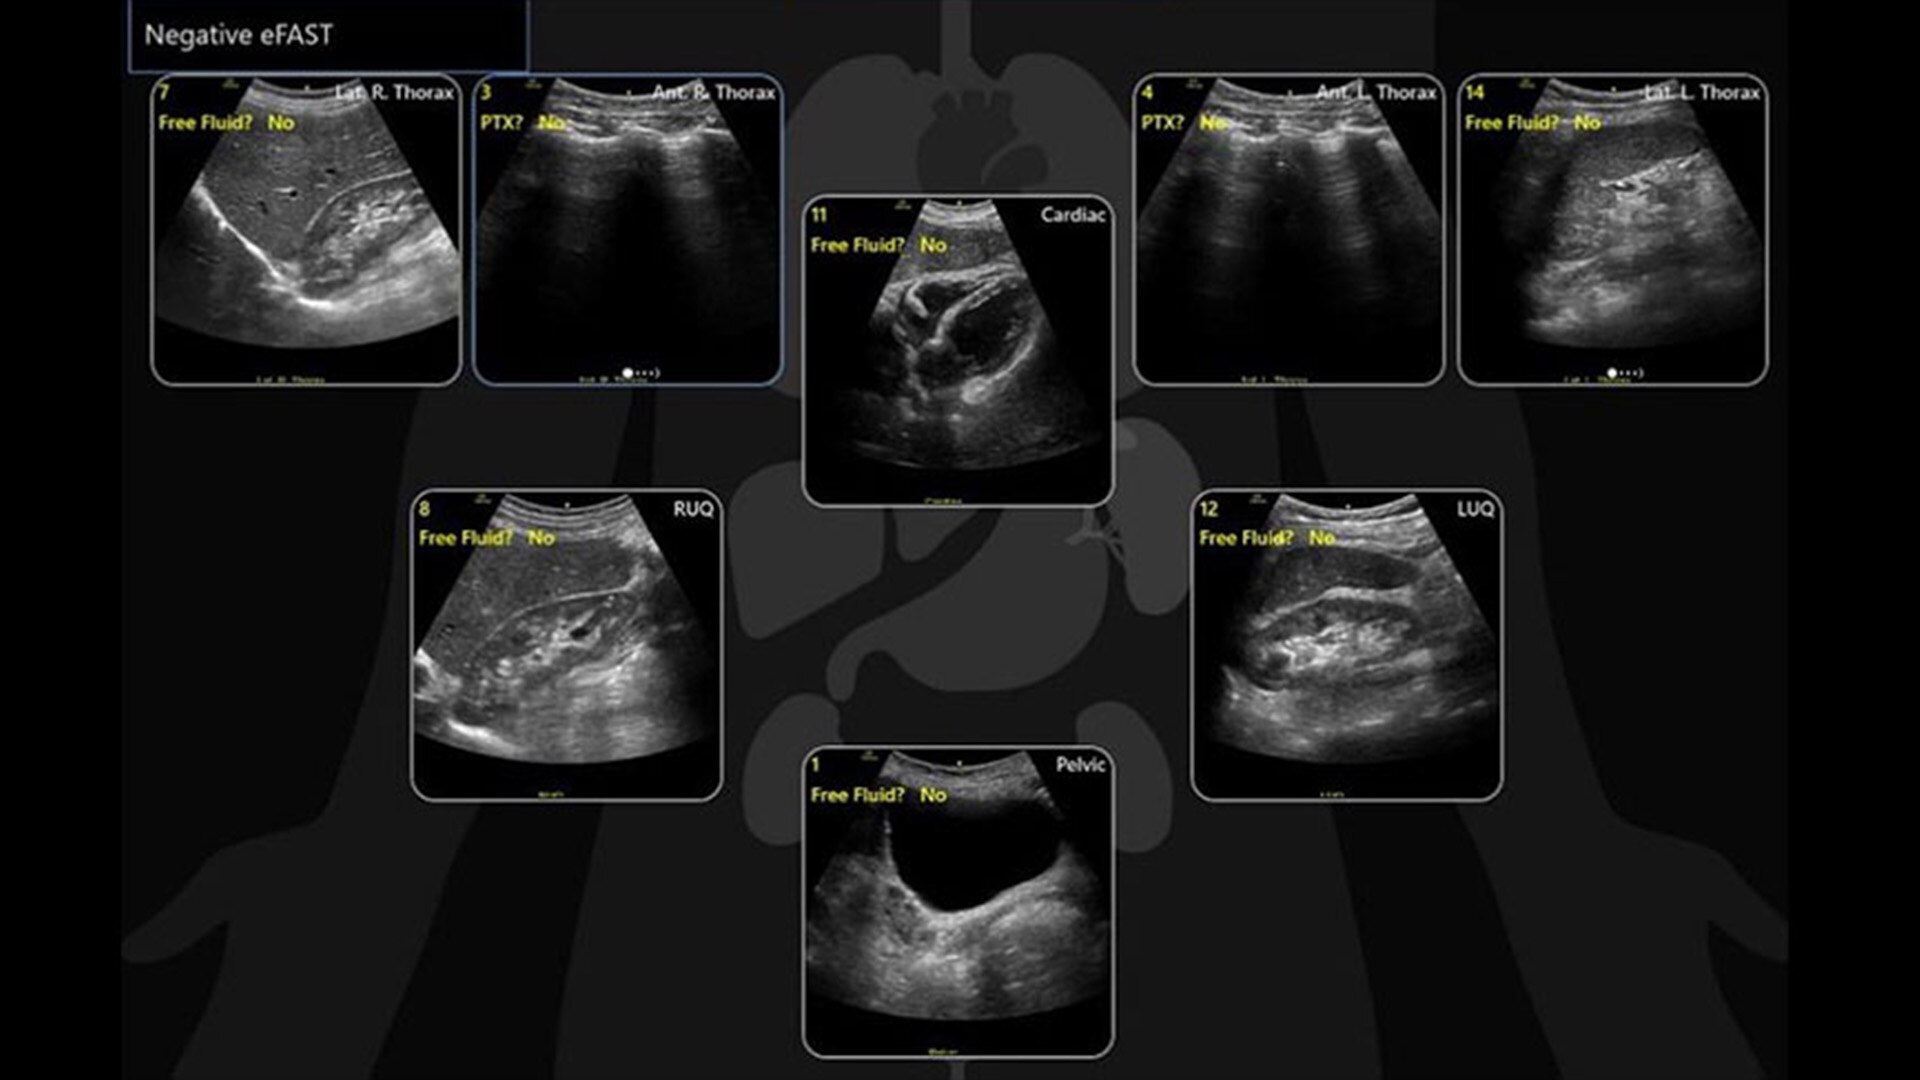

EFAST TOOL

A structured approach to trauma assessments

The eFAST tool helps you to quickly assess patient status, from internal bleeding to pneumothorax, and helps drive consistency from user to user by providing a way to reference multiple exams over time.

• Scan different zones sequentially, in a predetermined order, or in any order you desire.

• Document findings with single keystrokes and touch screen controls.

• Store images to a specific body zone by using a visual anatomical diagram, with next step recommendations provided.

• Label each zone with the relevant finding while scanning.

• View a summary review screen during or after the exam, showing the stored images superimposed over the anatomical diagram.